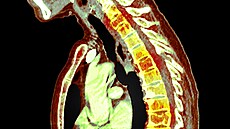

Ještě týž večer mi udělali magnetickou rezonanci a rentgen. Diagnóza: vyhřeznutí plotýnky s četnými fragmenty a co nejdříve operace. To už mi věřili, že je to vážné a že zřejmě trpím.